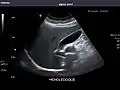

Gallbladder: No stones, wall thickening, or pericholecystic fluid.

Gallbladder